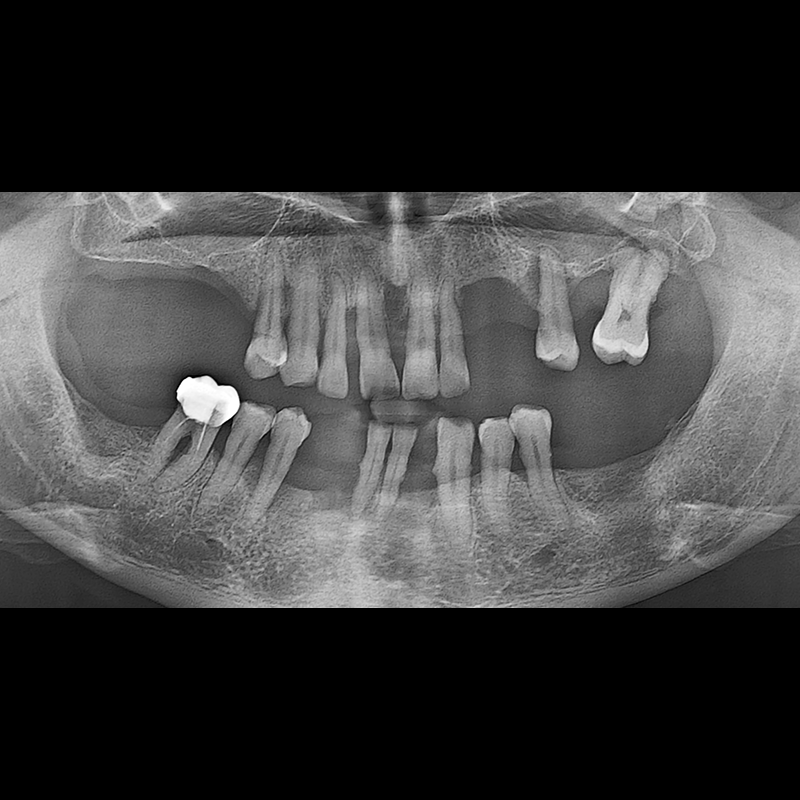

BEFORE AFTER

インプラント手術事例 2025.05.30

欠損した歯の部分と、生かしにくい歯の位置にインプラントを植立しました。